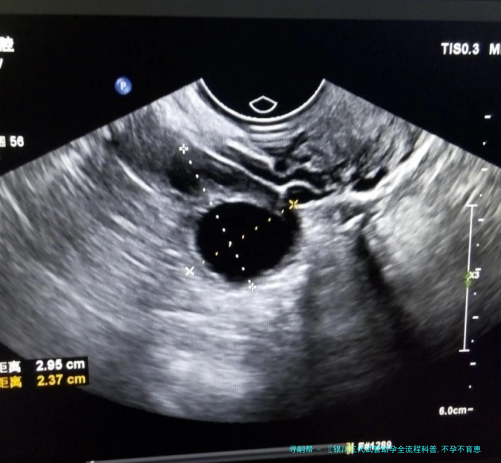

医生会陆续监测卵泡的大小和数量,认为最完美取卵时间。这个过程通常须要15-二十天,要求患者严格依照医嘱协同治疗。

取卵手术通常在静脉下进行,患者不会感应疼痛。医生在超声波引导下,用细针将卵子抽拿出来,全部过程安全可控。

胚胎移植前,病患须要接收子宫腔内环境检查。如果察觉左右成功率的疾病,应当先将胚胎冷冻保存,等病症治愈后再进行移植。